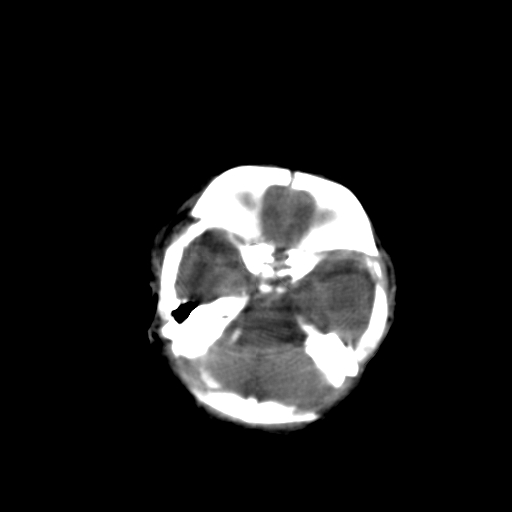

男,2天,孕31周早产儿,出生后窒息3分钟,精神反应差。

脑实质弥漫低密度,灰白质界限不清:结合临床考虑重度hie